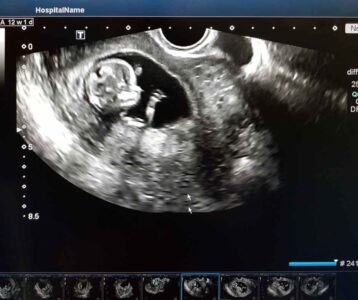

What Is the First Trimester?

The first trimester is the earliest phase of pregnancy, from week 1 to the end of week 12. In this time, your baby’s organs begin to form and your hormones change rapidly. That hormonal rollercoaster is exactly why the first trimester can feel intense—physically and emotionally. Mayo Clinic